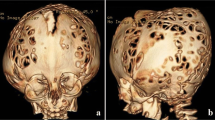

Calvarial defects have been reported in some patients with NF-1 too (Fig. 2) [37].